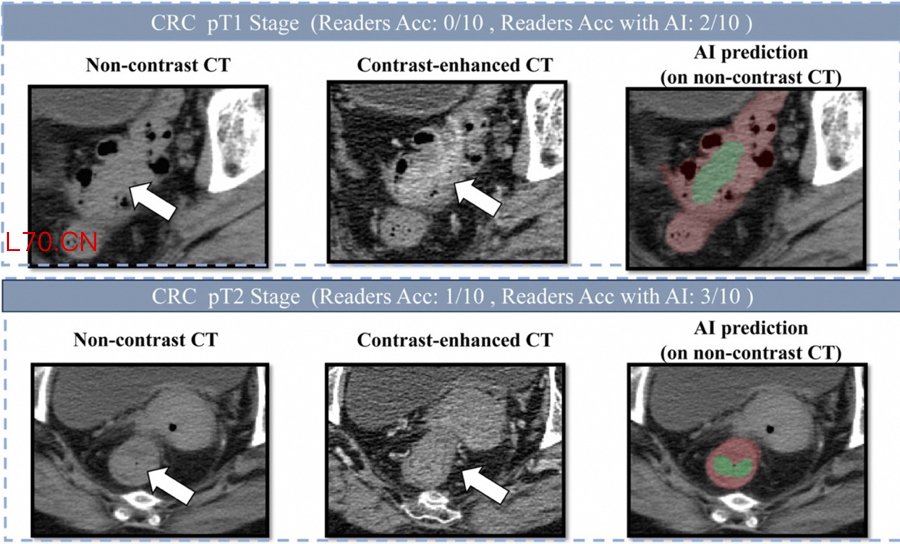

肠癌病灶在平扫CT、增强CT和AI画面上的表现

研究团队发表在欧洲肿瘤内科学会官方期刊《肿瘤学年鉴》(Annals of Oncology,影响因子65.4)上的论文显示,DAMO COCA模型的敏感性(即防止漏诊的能力)达到86.6%,特异性更达到99.8%,即误诊率仅有0.2%。与10名不同年资的影像科医生相比,DAMO COCA模型的敏感性显著高出20.4%,在乙状结肠、直肠等易漏部位上的表现尤为突出。而在AI辅助下,医生的敏感性和特异性可分别提高14.5%和3.1%,有效减少临床漏诊。